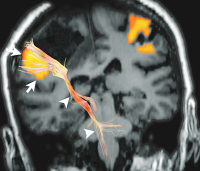

Figure 4: Combined fMRI and DTI tractography in a coronal view of a patient with a tumour near the primary motor cortex. Displacement of both the primary motor cortex (arrows) and the corticospinal tract (arrowheads) is seen.

Keywords: brainfMRITumor